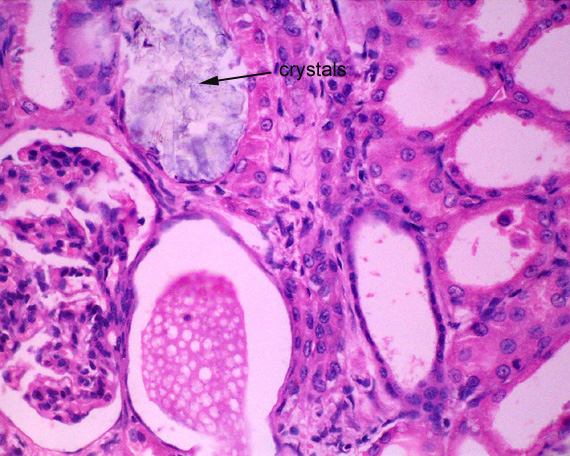

The birefringent crystals are more obvious when the section is viewed with the iris diaphragm of the microscope closed to reduce the light and increase the contrast.